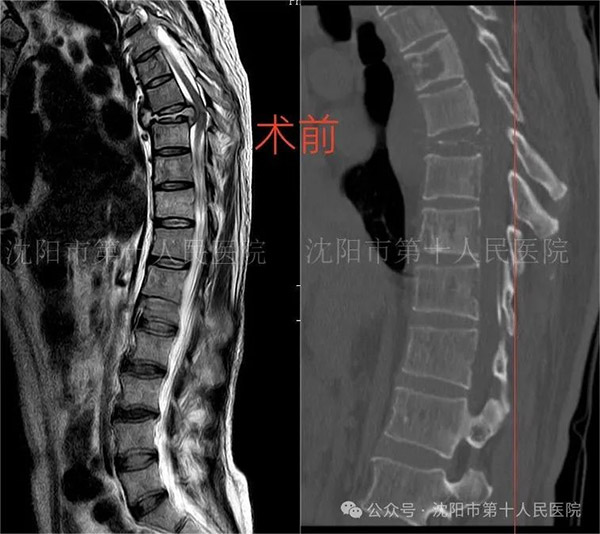

近日,四十六岁的吴先生在沈阳市第十人民医院(沈阳市胸科医院)成功接受了胸椎结核病灶清除椎间植骨融合椎弓根钉内固定术,术后恢复良好。

在麻醉科的积极配合下,手术如期进行。术中清除病灶、椎管减压、解除神经压迫、应用3D打印椎体植入病灶间,手术进行了4个多小时,取得圆满成功。术后转入ICU病房进一步支持治疗,病情趋于稳定后转回本科病房。终于再次见到生的希望,吴先生及家人对脊柱外科团队、麻醉科、ICU病房全体工作人员表达了深深的感谢和敬意,感谢全体医护的辛勤付出。吴先生回到脊柱外科病房后激动的说,没有脊柱外科柳主任的担当与手术技术,他就没有了生的希望,所有为他手术保驾护航的相关医生,都好比是他的再生父母,让他重获新生。